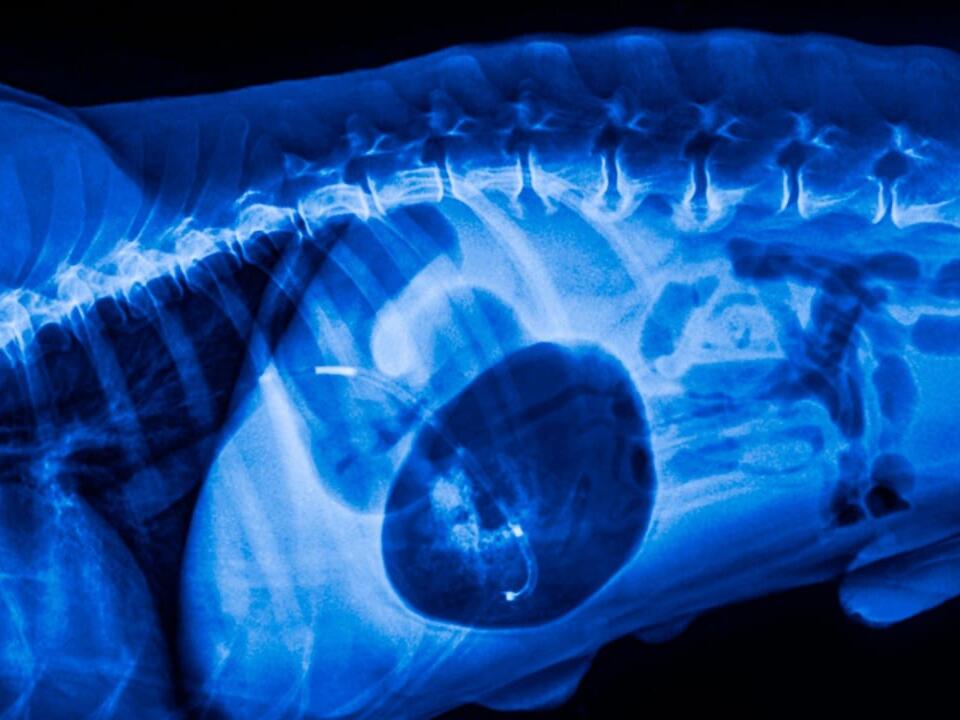

From todaysveterinarypractice.com

Diagnosing Canine Abdominal Organ Torsions Twisted in Every Way Is A Twisted Stomach Painful In Dogs As the stomach becomes distended, it usually. a dog stomach flip is a serious condition that affects a dog’s digestive system and is known by many different names, such as gastric. in some cases, the dog's stomach will rotate or twist. gdv is an emergency situation in which a dog’s stomach becomes twisted. It traps blood in. Is A Twisted Stomach Painful In Dogs.